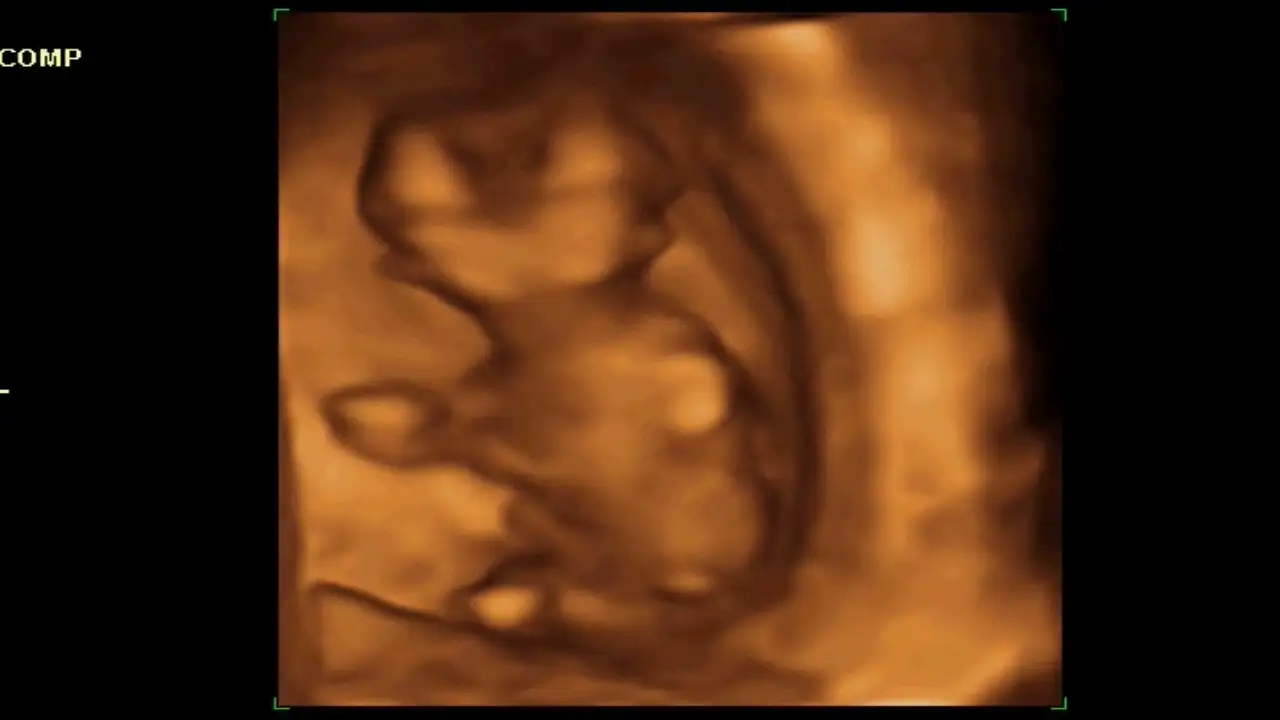

Kızlar merhaba, en son ikili tarama için doktora gittiğimde (12haftalikken) bana verilen 4 boyutlu görüntülerin resmini gönderiyorum sizlere.o gün doktor ile cinsiyet muhabbeti yaparken tahmin için çok erken olduğunu fakat pipi gibi bir çıkıntı görmediğini söyledi.6 Kasımda randevum var o zaman tam 16 haftanın başında olacağım umarım belli olur.ama meraklanmamak , hazırlıklara başlamak için sabirsizlanmamak elde değil :( sizlerden tahmin yürütebilecek var mı ?? :)